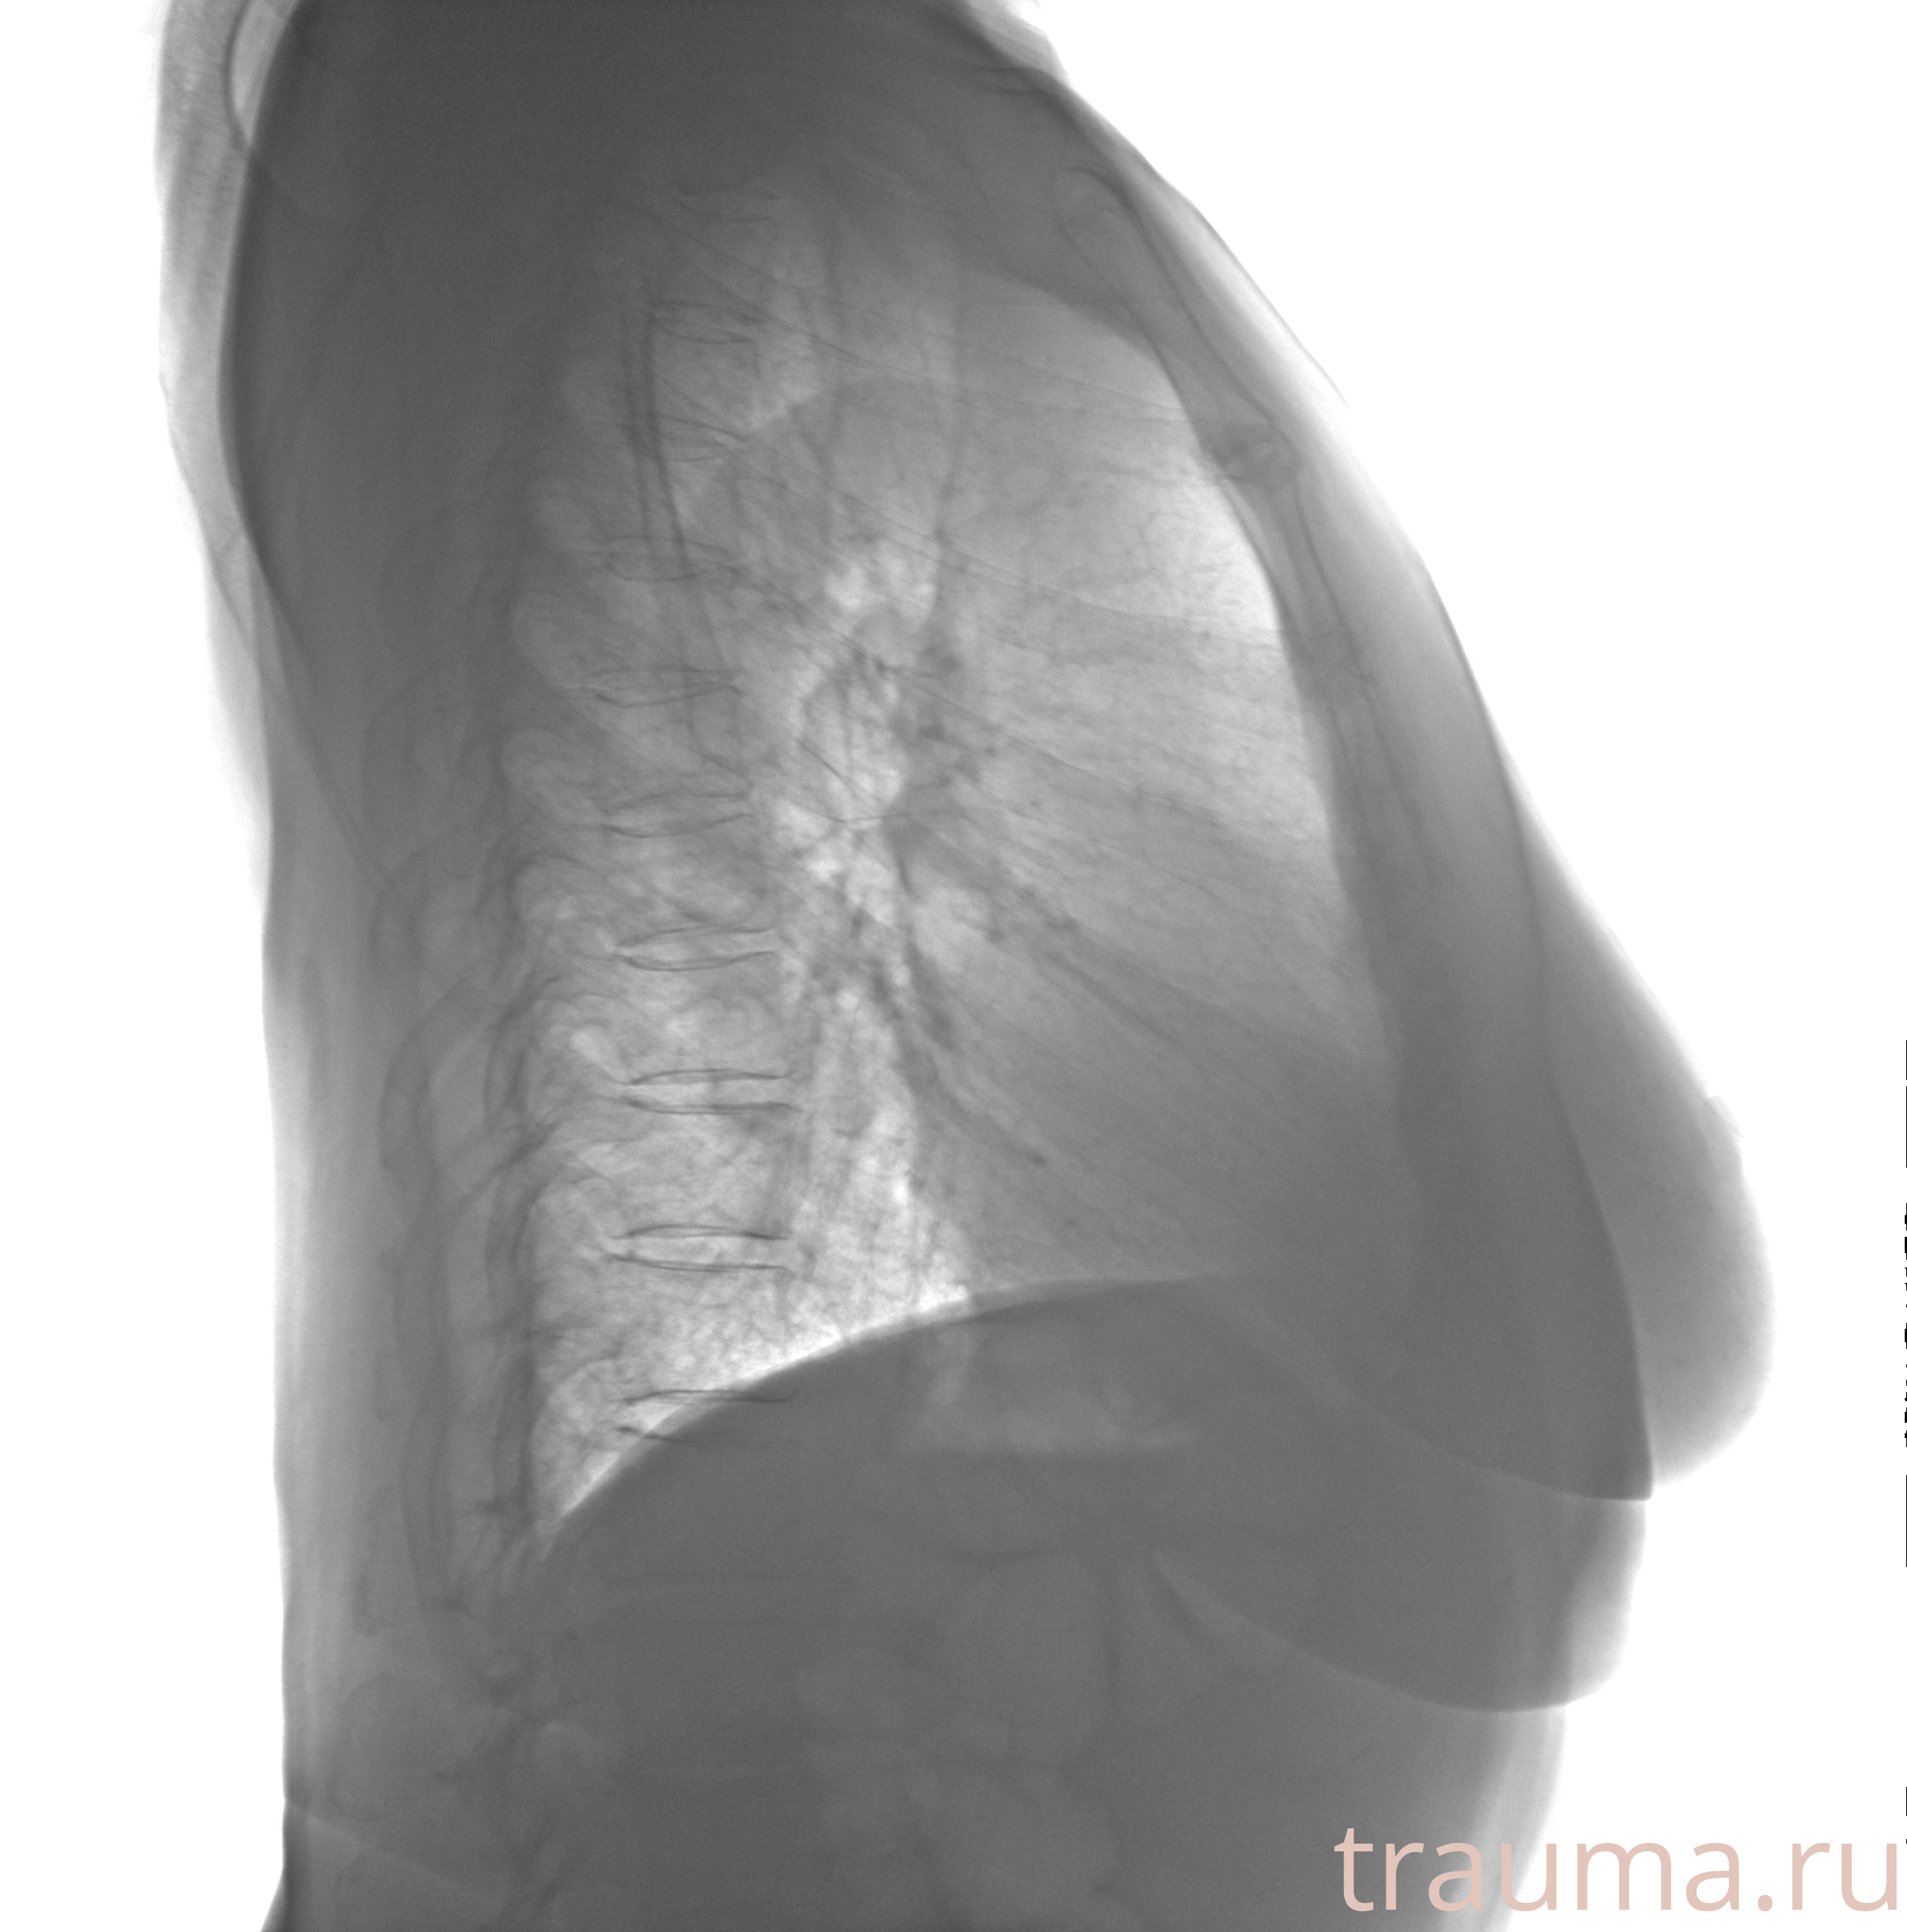

Рентген на дому: по вашему адресу приезжает врач-рентгенолог, травматолог-ортопед с мобильным рентгеновским аппаратом, проводит диагностику травмы или заболевания, делает необходимые рентгенограммы, дает рекомендации по дальнейшему лечению. Получить качественные снимки в домашних условиях возможно благодаря уникальной методике, разработанной МосРентген Центром для института  Склифосовского

при переломе шейки бедра и пневмонии от компании МосРентген Центр - партнера Института имени Склифосовского